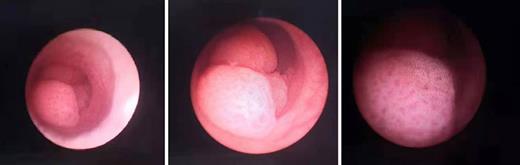

Three months later, urethrocystoscopy was performed for postoperative check, and a cauliflower-like neoplasm was found 1 cm away from the left ureteral orifice in the bladder (shown in Fig. 2). The renal pelvis was also checked, but there was no neoplasm in it. Biopsy was taken from the neoplasm in the bladder, and later pathological finding showed that it was urothelial carcinoma in situ. Five days later, transurethral resection of bladder tumor (TURBT) was conducted.

A cauliflower-like neoplasm was found 1 cm away from the left ureteral orifice in the bladder.